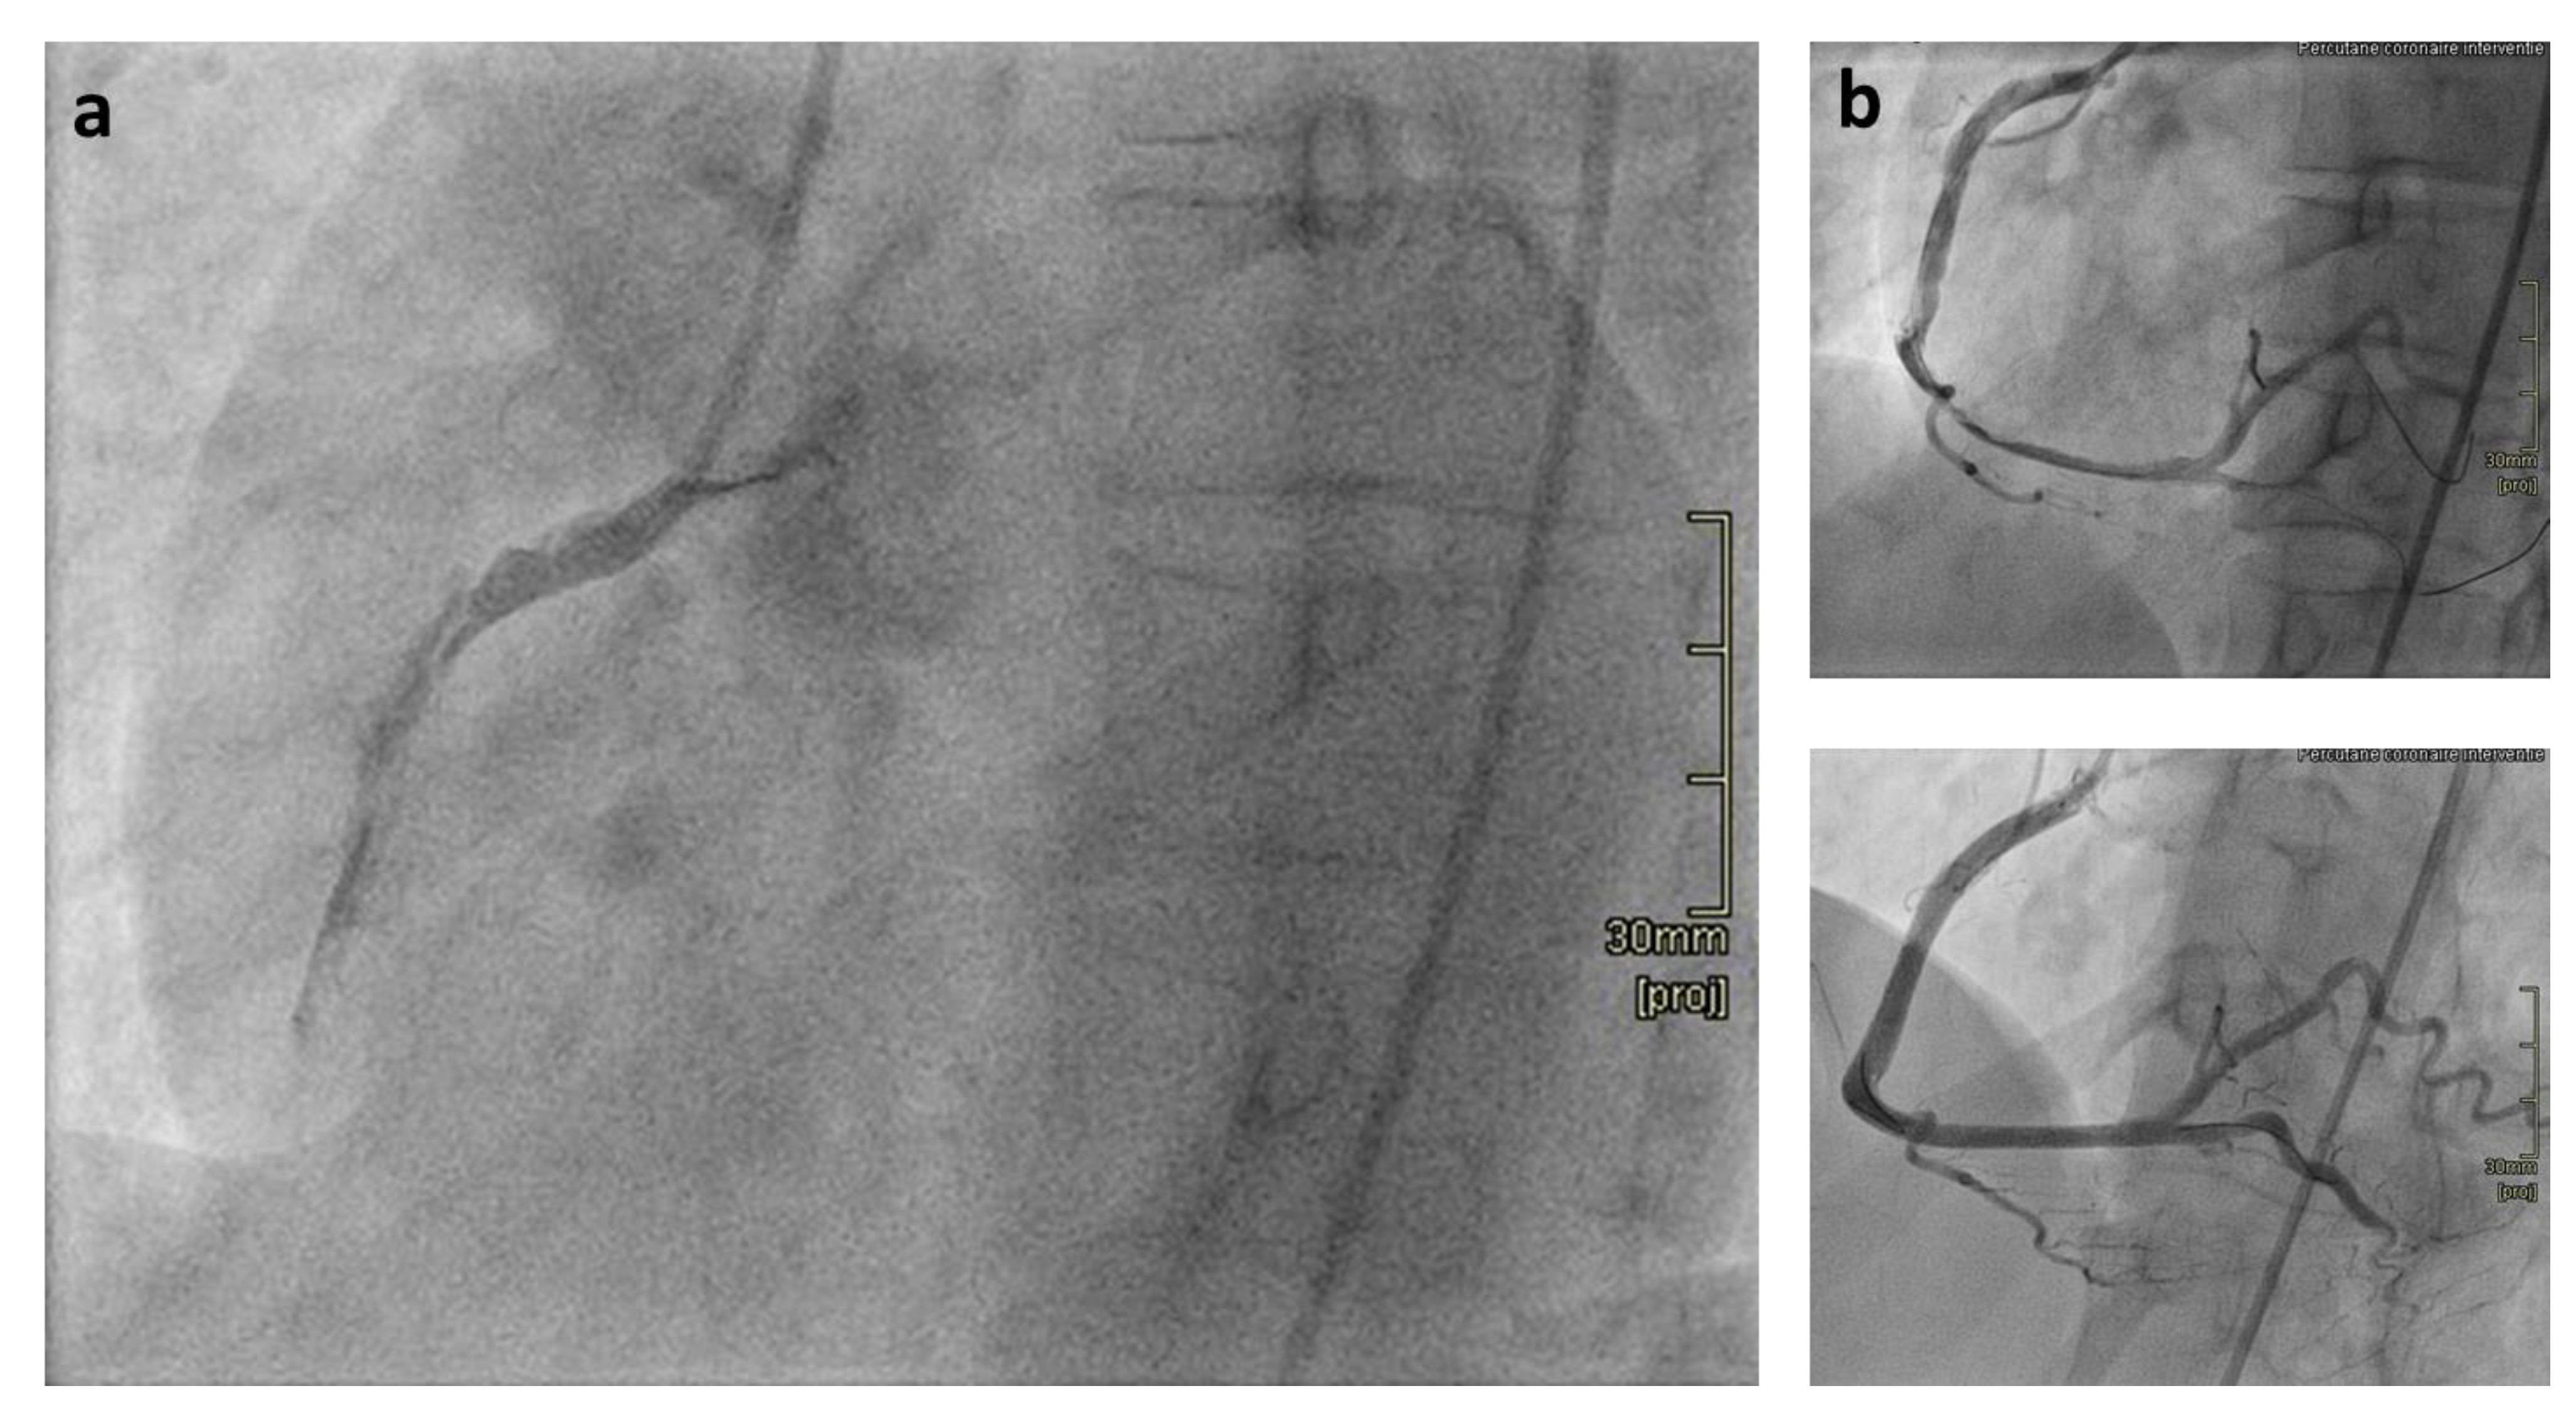

Case. A 33-year-old previously healthy woman presented with sudden onset chest pain. She was diagnosed with a myocardial infarction caused by SCAD. She was treated successfully by percutaneous coronary intervention with placement of four stents (Figure 1). Since in a minority of patients a spontaneous arterial dissection is caused by an underlying genetic cause, she was referred for genetic counselling. Her medical history (including two uncomplicated pregnancies), family history, and physical examination did not reveal any further signs indicating a connective tissue disorder or hereditary kidney disease. The prior risk of a genetic cause therefore was low. A previously reported heterozygous pathogenic variant, c.1744G >A p.(Gly582Ser) in the COL3A1 gene was identified using targeted next generation sequencing analysis of 21 genes associated with aortic dilatation and Marfan-like syndromes, confirming the diagnosis of vEDS. Establishing the diagnosis allowed for disease specific recommendations including vascular imaging, strict regulation of blood pressure, and additional vascular imaging. Regulation of blood pressure was first attempted with celiprolol, as suggested by the BBEST study, but was switched to atenolol due to side effects (frequent headaches) [5]. MRA was performed and no other arterial aneurysms or dissections were present. The patient remains under regular surveillance. Relatives were offered the option of pre symptomatic genetic testing.

Figure 1. (a) Type F coronary dissection, caused by a Type 4 SCAD, of the right coronary artery (RCA) before intervention; TIMI flow grade 0. (b) Above Restoration of flow after wiring, however widespread coronary dissection and diminished coronary flow remain. Below Result after percutaneous coronary intervention with four drug-eluting stents with restoration of coronary flow.